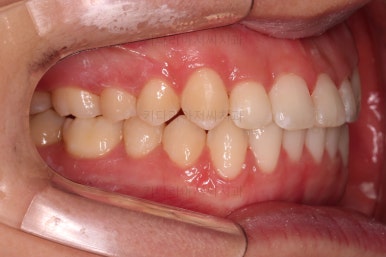

초진 시 입안의 모습이에요.

입을 다물고 있을 때는 자연스러운 다물림이나 옆라인 등 모두 양호해요.

입을 벌리거나 말할 때는 앞니가 삐뚤고 덧니가 있어 미적으로 좋지 못하네요.

위아랫니가 모두 삐뚤어요.

특히 앞니가 삐뚤고 위아래 앞니가 고르게 덮여있는게 아니라 뒤죽박죽 엉켜있어서 치아의 마모도 굉장히 많이 되어있는 상태였어요.

이번 환자분은 치아가 삐뚤어 있는 양 + 돌출감을 고려했을 때 비발치로 가능할 것이라고 판단이 되었어요.

굳이 입이 들어가길 원하시거나 혹은 교정 중에 튀어나온다고 느끼신다면 사랑니 자리를 확보해 통째로 뒤로 살짝 밀언허는 방법도 있기 때문에 비발치 교정을 추천드렸어요.